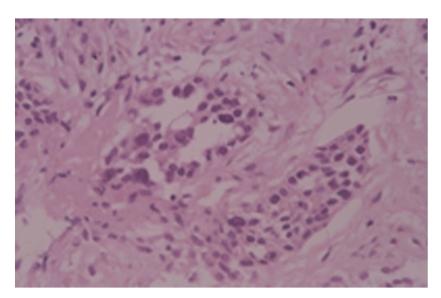

Metastases from a variety of malignant tumors can involve the ureters, but ureteral involvement by lung cancer is extremely rare and usually described at autopsy. We report a rare case of a 76-year-old man who presented with a three-month history of right flank dullness and was noted to have a nonhomogeneous retroperitoneal mass with hydronephrosis of the right kidney on computed tomography of the abdomen. Computed tomography of the thorax showed a nodule in the lower lobe, measuring 3 × 2 cm, in the right lung. After excluding the presence of other primary tumors and metastases, we reached a final diagnosis of solitary retroperitoneal metastasis of adenocarcinoma of the lung. Although rare, in patients of non-small cell lung cancer, presence of hydronephrosis should alert the physician to the possibility of metastasis.

摘要

多种恶性肿瘤的转移灶可累及输尿管,但肺癌累及输尿管极为罕见,通常在尸检时才被描述。我们报告一例罕见病例,一名76岁男性,有三个月的右侧腰部钝痛病史,腹部计算机断层扫描显示有一个不均匀的腹膜后肿块,右肾积水。胸部计算机断层扫描显示右肺下叶有一个3×2厘米的结节。在排除其他原发性肿瘤和转移灶后,我们最终诊断为肺腺癌孤立性腹膜后转移。虽然罕见,但在非小细胞肺癌患者中,出现肾积水应提醒医生注意转移的可能性。